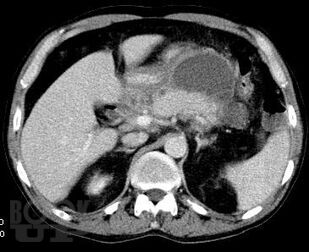

Учебно-методическое пособие посвящено актуальным проблемам этиологии, патогенеза, диагностики, современным методам консервативного и оперативного лечения острого панкреатита Представлены новые классификации, схемы консервативного лечения, современные виды оперативного лечения. Иллюстрировано рисунками, таблицами, имеются тестовые задания и задачи. Пособие предназначено для ординаторов и слушателей дополнительного профессионального образования, обучающихся по специальности 31.08.67 Хирургия.